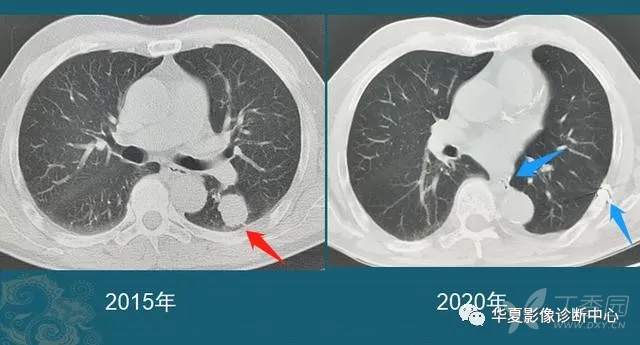

我们每年都能发现很多从肺小结节长大的肺癌,挑出两个速度最快的分享一下:

这是一位老年男性,有吸烟史,也是在两年多的时间内,肺结节从不足3mm长到1cm以上,后来病理确诊肺鳞癌。

中老年人定期胸部CT体检,可以及时发现这些生长较快的恶性肺结节,予以手术根治。